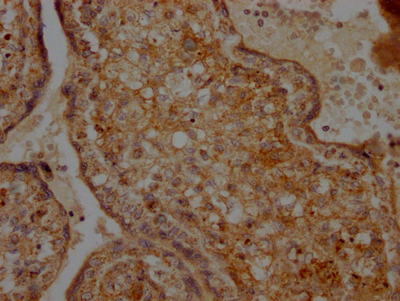

IHC image of CSB-RA441307A0HU diluted at 1:100 and staining in paraffin-embedded human placenta tissue performed on a Leica BondTM system. After dewaxing and hydration, antigen retrieval was mediated by high pressure in a citrate buffer (pH 6.0). Section was blocked with 10% normal goat serum 30min at RT. Then primary antibody (1% BSA) was incubated at 4℃ overnight. The primary is detected by a Goat anti-rabbit IgG polymer labeled by HRP and visualized using 0.05% DAB.